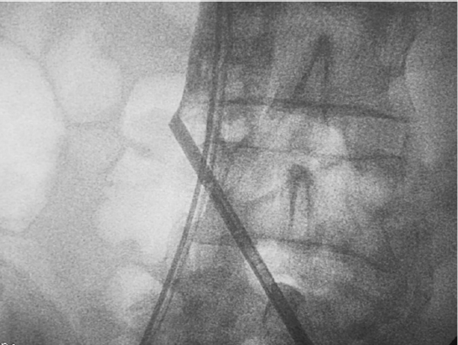

Figura 3 Una vez lograda la hemostasia se desplazó el balón y se infló nuevamente por encima del sitio de la perforación, con el fin de hacer una nueva inyección de contraste con la vena cava ocluída casi en su totalidad en búsqueda de fugas remanentes. Al no observar fugas, se consideró que la hemostasia había sido adecuada.